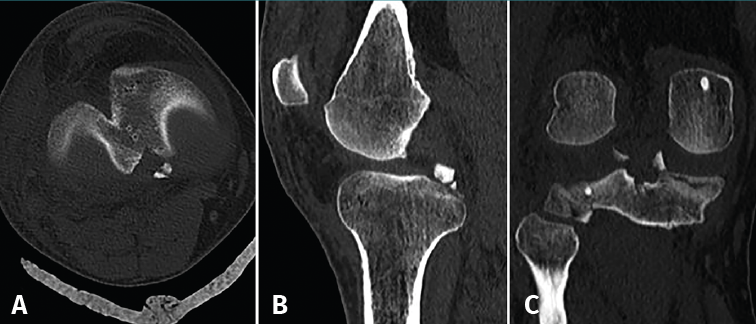

La artroscopia confirmó el diagnóstico mediante la visualización de la raíz avulsionada junto con el fragmento óseo a nivel medial (Figura 4A) y la lesión radial de la raíz externa (Figura 5). La palpación de ambas raíces mostraba una clara inestabilidad. El LCA estaba muy afectado, con una rotura subtotal, mientras que el LCP presentaba una correcta estabilidad a la palpación y testado.

Figura 5. Imagen artroscópica desde el portal anterolateral donde se identifica la lesión radial de la raíz del menisco externo.